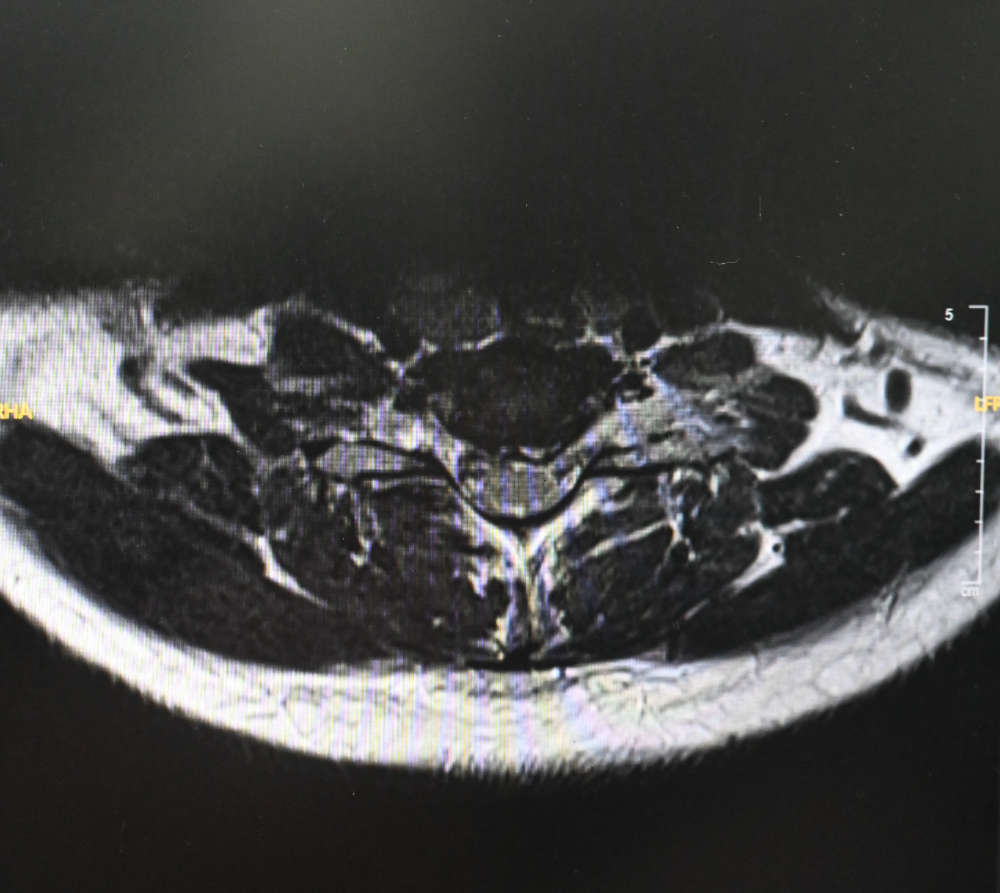

Upon arrival, Dr. Garg performed a detailed evaluation, including clinical examination and advanced imaging. She was diagnosed with a C6–C7 cervical disc prolapse — a condition where the disc in the neck bulges out and compresses the spinal nerves, causing neck pain and arm pain (cervical radiculopathy).

Given the severity of her symptoms and the long duration of suffering, Dr. Garg recommended Anterior Cervical Disc Replacement (ACDR) at the C6–C7 level, a modern motion-preserving spine surgery.